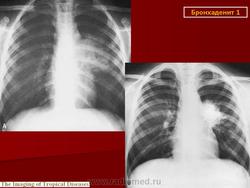

Различают инфильтративный, опухолевидный и малые формы туберкулеза внутригрудных лимфатических узлов. Опухолевидная форма проявляется увеличением размеров лимфатических узлов в результате воспалительной гиперплазии, что обнаруживается при рентгенологическом исследовании. Контуры лимфатических узлов на рентгенограмме и томограммах четкие. Инфильтративный туберкулез внутригрудных лимфатических узлов характеризуется не только увеличением узлов, но и развитием инфильтративных изменений в легочной ткани, в прикорневых ее отделах. Малые формы проявляются незначительным увеличением внутригрудных лимфатических узлов, что выявляется главным образом на томограммах с поперечным размазыванием в прямой или боковой проекциях. Этот вариант заболевания в последнее время встречается чаще, чем в прежние годы.

Рис. 1а, б. Верхняя доля правого легкого уменьшена в объеме, однородно уплотнена. Нижний контур доли вогнутый. Органы средостения в верхнем отделе умеренно смещены вправо. Диафрагма на стороне поражения расположена выше обычного.

Рис. 2а, б, в, г. Компьютерные томограммы органов грудной клетки. На передней стенке правого главного бронха узелковые образования, перекрывающие частично просвет бронха. Верхнедолевой бронх нитевидно сужен. Верхняя доля правого легкого уменьшена в объеме, верхушечный и задний сегмент ателектазированы.